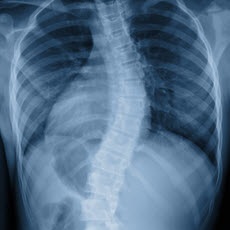

Scoliosis causes a sideways curve of your backbone, or spine. These curves are often S- or C-shaped. Scoliosis is most common in late childhood and the early teens, when children grow fast. Girls are more likely to have it than boys. It can run in families. Symptoms include leaning to one side and having uneven shoulders and hips. Sometimes it is easy to notice, but not always.

Children may get screening for scoliosis at school or during a checkup. If it looks like there is a problem, your doctor will use your medical and family history, a physical exam, and imaging tests to make a diagnosis. Treatment depends on your age, how much more you're likely to grow, how much curving there is, and whether the curve is temporary or permanent. People with mild scoliosis might only need checkups to see if the curve is getting worse. Others might need to wear a brace or have surgery.